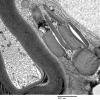

3 NORMAL MYELIN & SCHWANN CELLS

4 Pi Granules (of Reich)